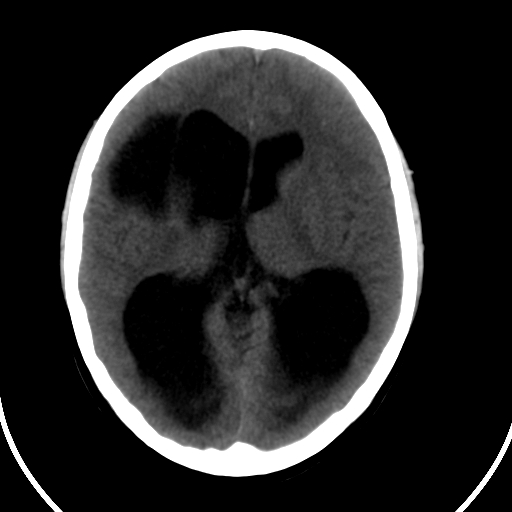

男,11岁

重度脑积水,但第四脑室扩大不明显,考虑导水管阻塞,建议mr。

阻塞性脑积水并脑裂畸形

右额叶内见一边界清楚,脑脊液密度的囊腔,无灰质内衬,并与脑室相通,四室以上脑室系统高度扩张。诊断:先天性脑穿通畸形伴梗阻性脑积水

脑穿通畸形并梗阻性脑积水.